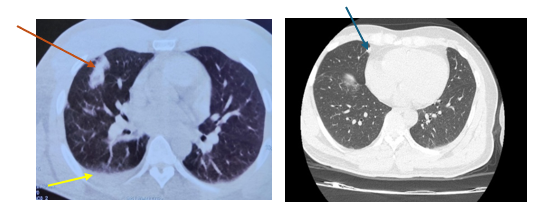

Hình 1: Hình ảnh cắt lớp vi tính lồng ngực: nốt tổn thương u phổi phải kích thước 10x25mm (mũi tên đỏ), dịch màng phổi phải (mũi tên vàng), tổn thương di căn phổi (mũi tên xanh)

Đến 6 tháng sau bệnh nhân đi khám sức khoẻ được chụp cắt lớp vi tính lồng ngực cho kết quả: Vài nốt đặc thùy giữa và dưới phổi phải, nốt lớn kích thước 10x25mm, tràn dịch màng phổi phải => vào Trung tâm Y học hạt nhân và Ung bướu đánh giá và điều trị